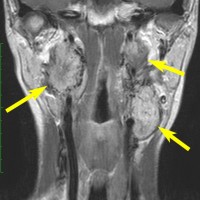

遺伝歴があり30代くらいです。黄色の矢印で示す右側はglomus vagale,左側は上がglomus jugulare、左下がglomus caroticumです。教科書に載せたいくらい典型的な部位に発生しています。無症状ですからもちろん治療はしません。6年くらい経過観察していますがほとんど増大もしません。